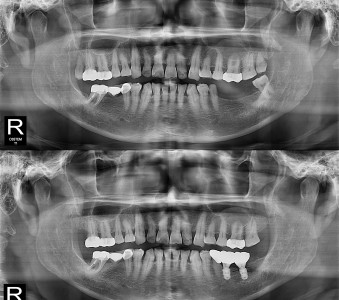

결과로 증명합니다.

국제모아치과의

실제 임상 증례